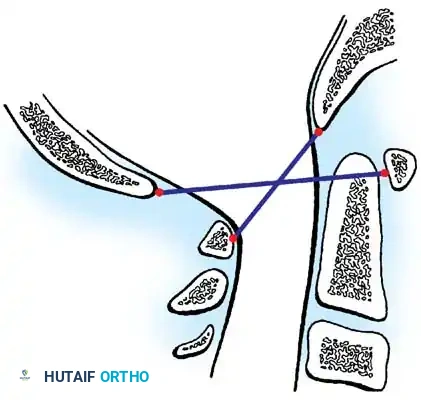

3. Powers Ratio

The Powers ratio is the most widely utilized metric for diagnosing anterior or posterior atlantooccipital translation. It is calculated by drawing two lines:

1. Line BC: From the Basion (B) to the posterior arch of the atlas (C).

2. Line OA: From the Opisthion (O) to the anterior arch of the atlas (A).

The length of line BC is divided by the length of line OA (BC/OA).

* Normal: ~0.77

* Anterior Translation: A ratio > 1.0 is diagnostic of abnormal anterior translation of the occiput.

* Posterior Translation: According to Parfenchuck et al., a ratio < 0.55 indicates abnormal posterior translation.

Fig. 37-36 Powers ratio. A ratio greater than 1 is diagnostic of anterior atlantooccipital translation, and a ratio less than 0.55 is diagnostic of posterior translation.